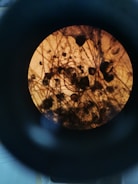

Microscope view of biological samples in a clinical lab.